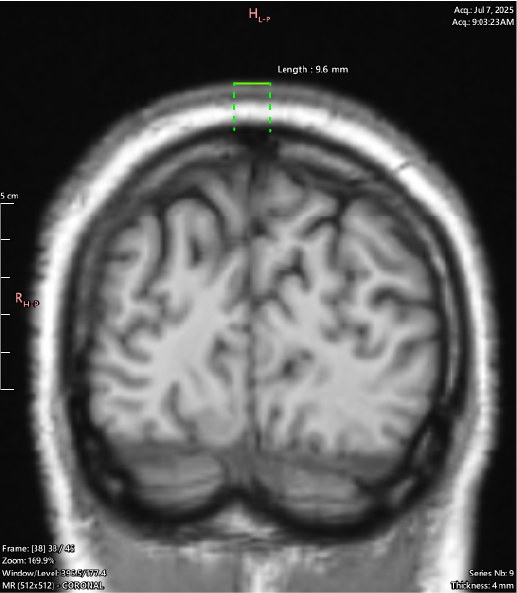

T1 Coronal

Coronal view shows this is happening along the Sagittal Suture - cranial sutures should return a uniform signal void (black) across all sequences as they are dense structures with little to no free water movement.

It can be seen throughout the JULY 2025 MRI series that a majority of the cranial sutures are instead filled with variable hypointense signaling describing dense, fibrous tissue.

By the age of 33 the cranial sutures should be almost - if not entirely - fused, showing as a thin (approx. 2mm) black zig-zag along their respective paths, if showing at all.

My Sagittal Suture in these images shows as 12.4mm wide at the outside margin, clearly showing atypical imaging presentation, indicating an underlying process occurring.